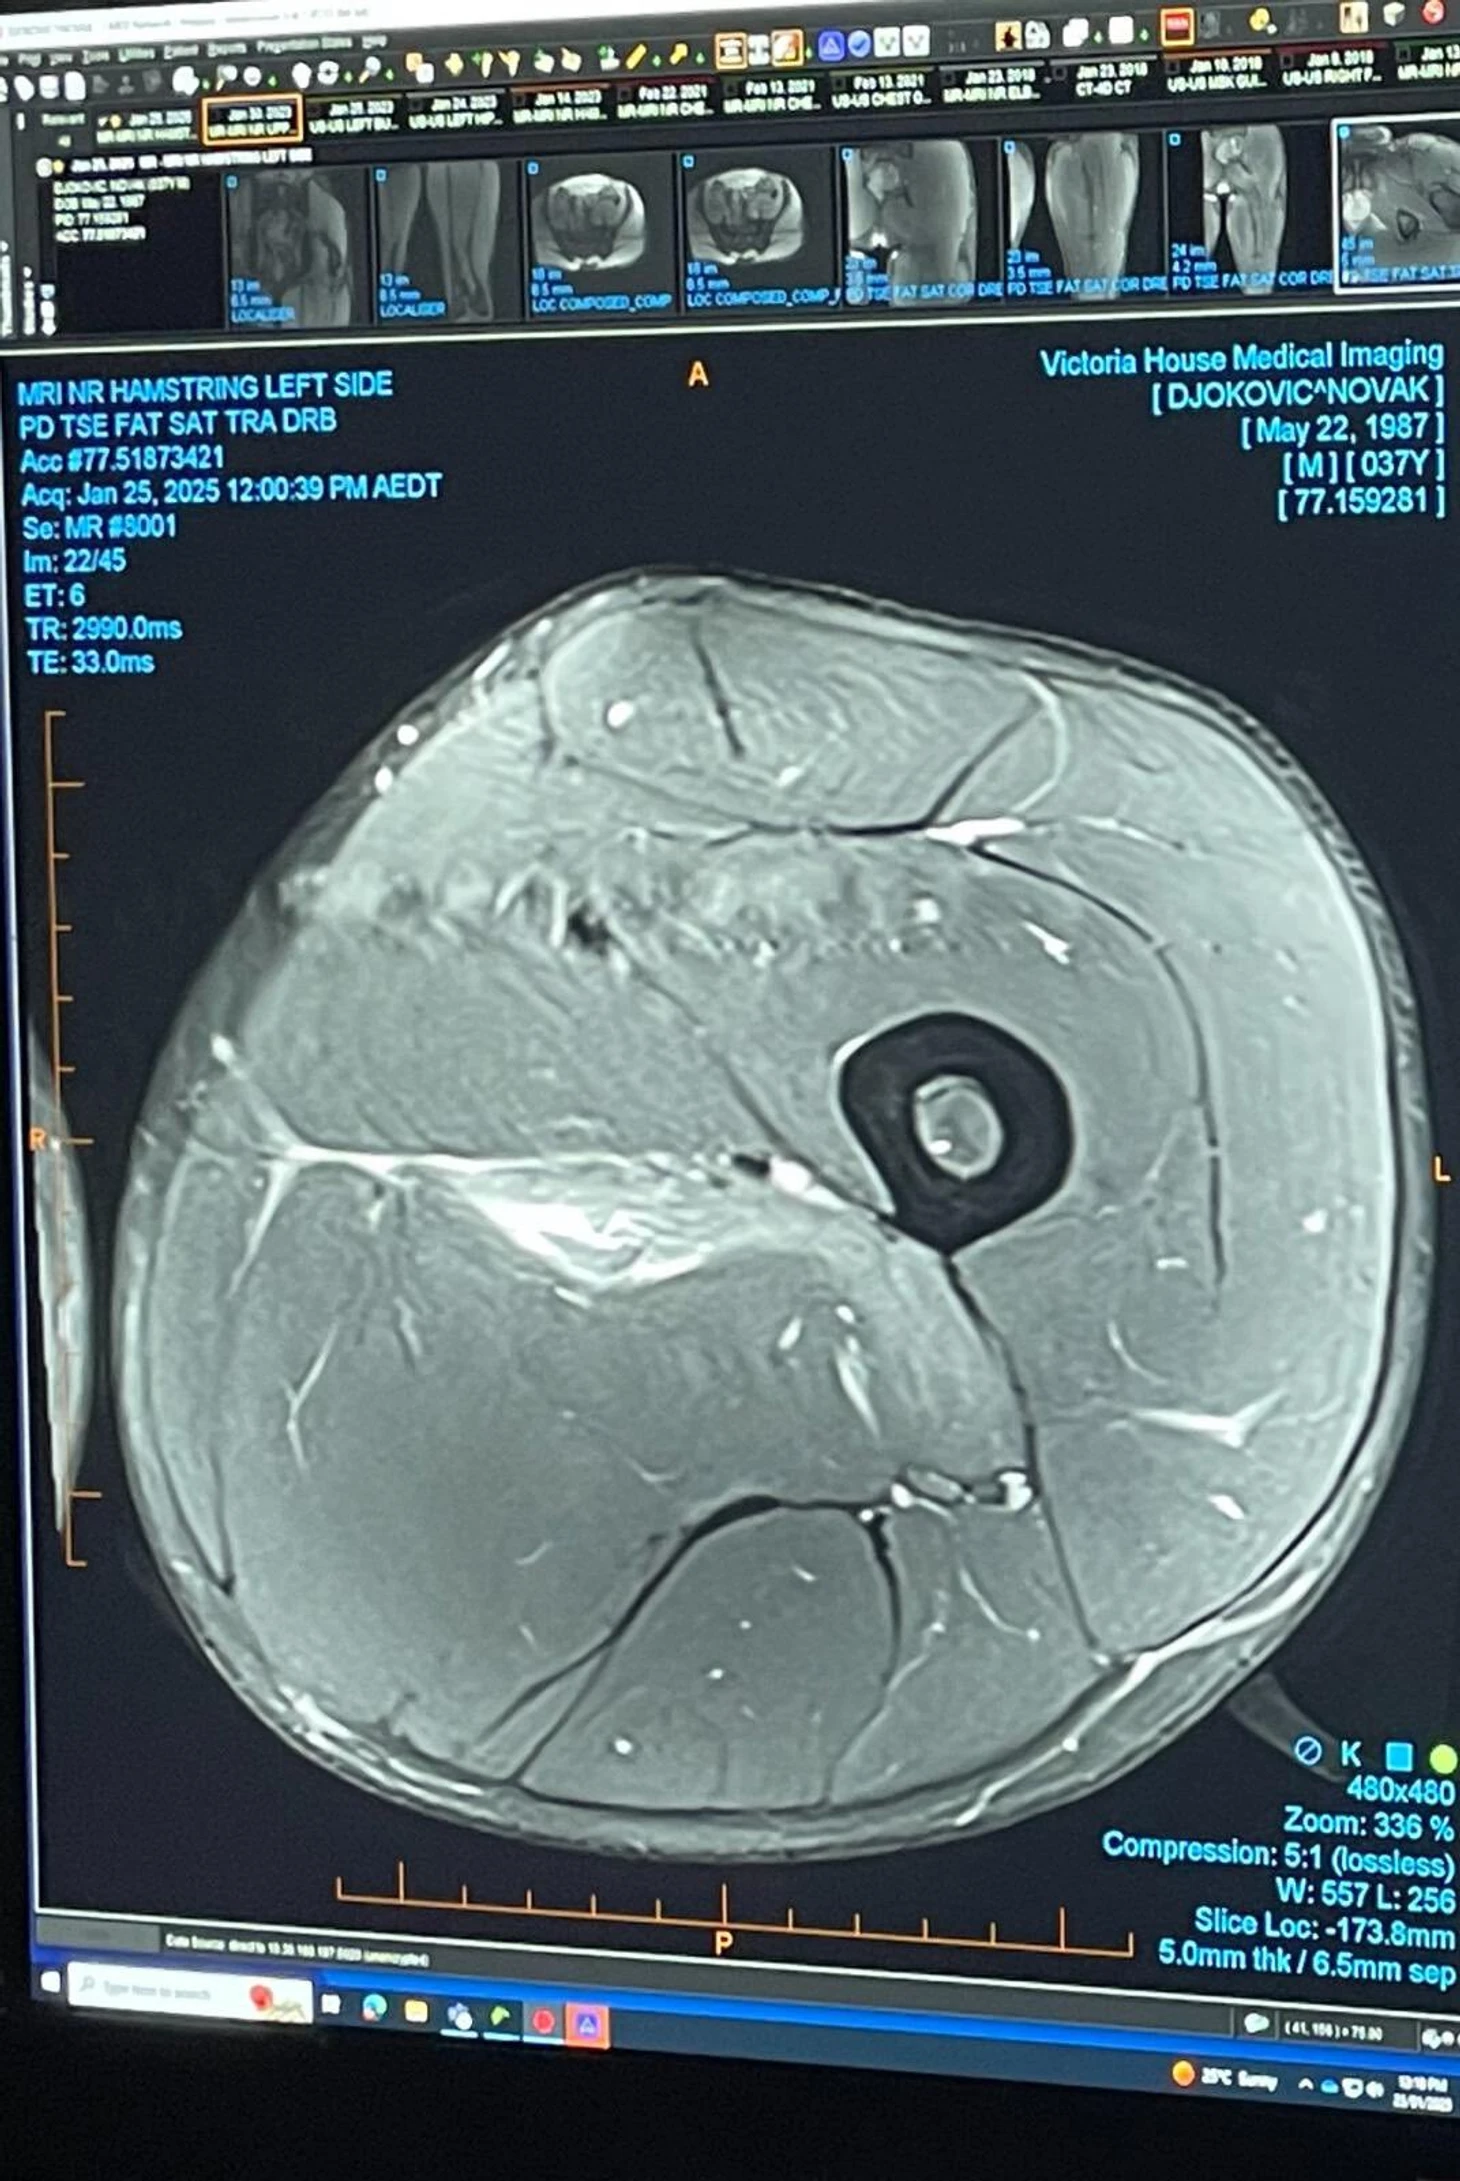

Джокович выложил МРТ левого бедра: «Решил показать это всем «экспертам» по спортивным травмам»

Новак Джокович выложил в твиттер МРТ левого бедра.

«Решил показать это всем «экспертам» по спортивным травмам», – подписал 24-кратный чемпион «Больших шлемов».

Вчера он снялся с полуфинала Australian Open, проиграв первый сет Александру Звереву, и рассказал, что у него надрыв мышцы.

Ранее некоторые, в частности Джон Макинрой и Борис Беккер, намекали, что серб мог использовать травму как тактический прием по ходу четвертьфинала против Карлоса Алькараса.